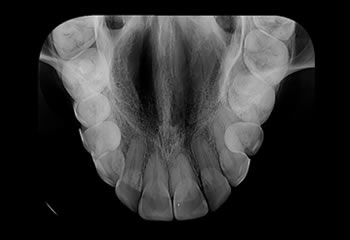

Radiografias Oclusais

Técnica radiográfica intrabucal, esta técnica possibilita uma visão em conjunto dos elementos dentais da região de incidência e tecido ósseo adjacente.